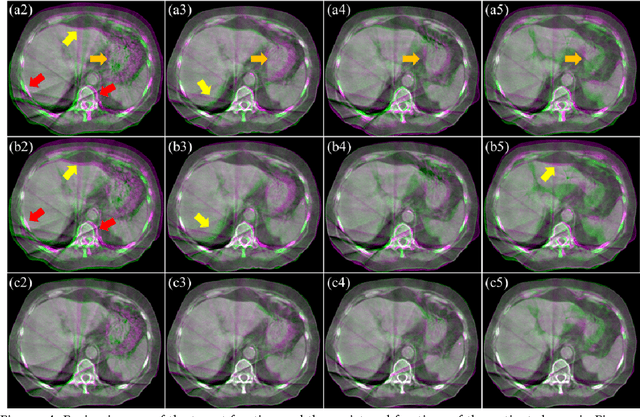

Abstract:This paper aims to create a deep learning framework that can estimate the deformation vector field (DVF) for directly registering abdominal MRI-CT images. The proposed method assumed a diffeomorphic deformation. By using topology-preserved deformation features extracted from the probabilistic diffeomorphic registration model, abdominal motion can be accurately obtained and utilized for DVF estimation. The model integrated Swin transformers, which have demonstrated superior performance in motion tracking, into the convolutional neural network (CNN) for deformation feature extraction. The model was optimized using a cross-modality image similarity loss and a surface matching loss. To compute the image loss, a modality-independent neighborhood descriptor (MIND) was used between the deformed MRI and CT images. The surface matching loss was determined by measuring the distance between the warped coordinates of the surfaces of contoured structures on the MRI and CT images. The deformed MRI image was assessed against the CT image using the target registration error (TRE), Dice similarity coefficient (DSC), and mean surface distance (MSD) between the deformed contours of the MRI image and manual contours of the CT image. When compared to only rigid registration, DIR with the proposed method resulted in an increase of the mean DSC values of the liver and portal vein from 0.850 and 0.628 to 0.903 and 0.763, a decrease of the mean MSD of the liver from 7.216 mm to 3.232 mm, and a decrease of the TRE from 26.238 mm to 8.492 mm. The proposed deformable image registration method based on a diffeomorphic transformer provides an effective and efficient way to generate an accurate DVF from an MRI-CT image pair of the abdomen. It could be utilized in the current treatment planning workflow for liver radiotherapy.